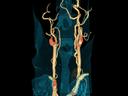

More and more radiologists are relying on the rich diagnostic possibilities offered by True Dual Energy imaging on Siemens Healthineers' CT scanner fleet ranging from SOMATOM® Scope Power up to the outstanding SOMATOM Force.

The question is: What makes True Dual Energy stand out? Look for these three criteria: crisp images with the option for even sharper contrast and significant artifact reduction; no extra dose in either Single Source or Dual Source Dual Energy scans, and a broad applicability for virtually all clinical questions and patients.

Discover Dual Energy (DE) spectral imaging. It’s the difference between images and answers. Visualization and characterization. Qualification and quantification. Built into all of our CT scanners, it delivers powerful performance, incredible versatility for your entire patient population, and exceptional ease-of-use – all while integrating seamlessly with your current workflow.